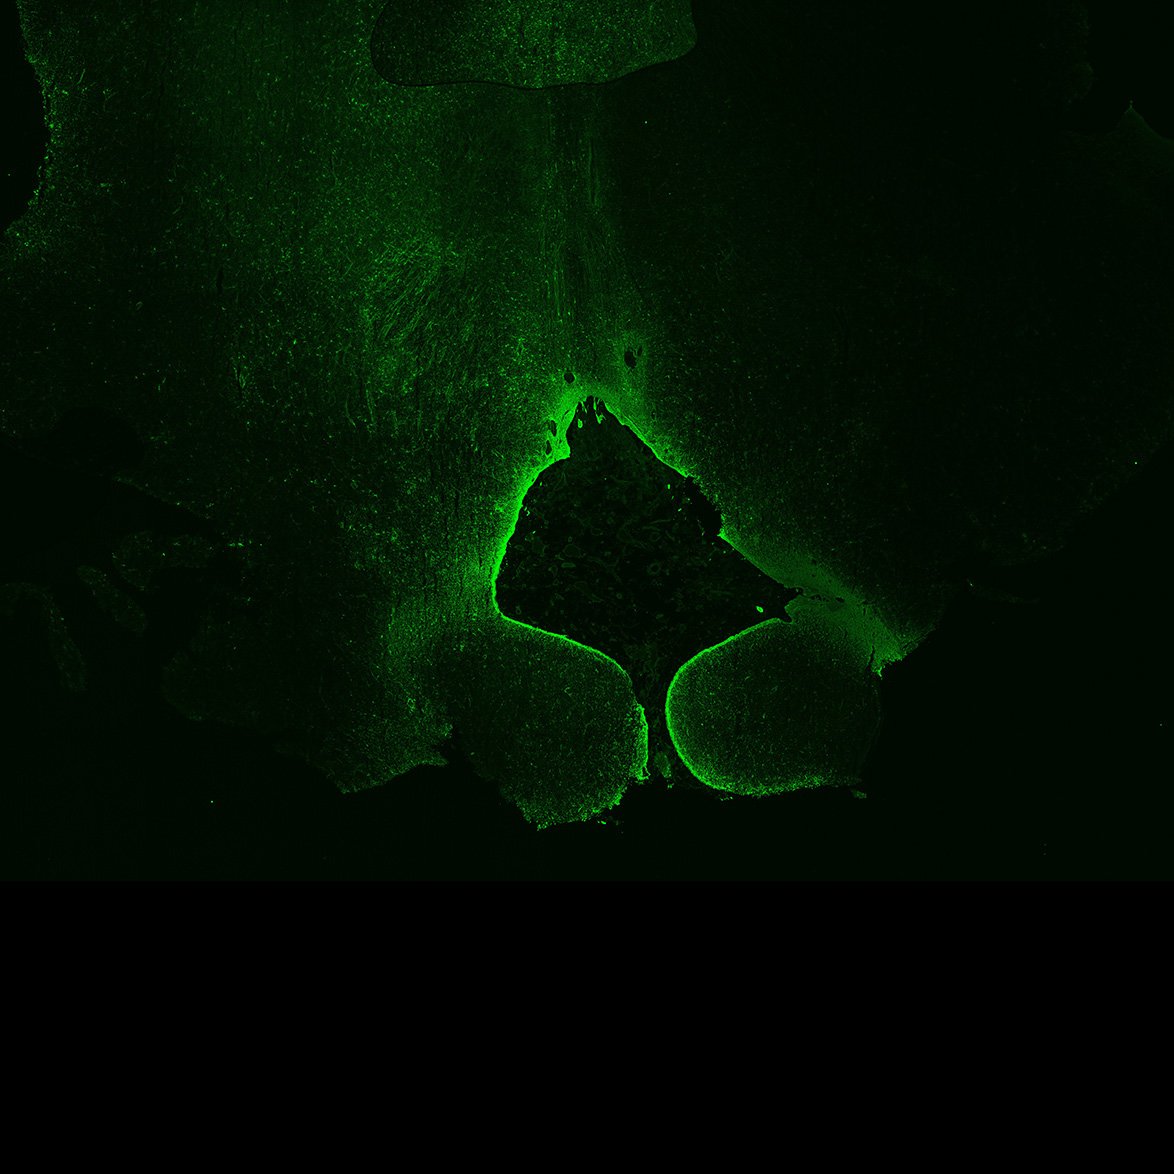

An anatomical analysis of the developing human midbrain from 6 post-conceptional weeks (PCW) to 22 PCW reveals increased tissue complexity, characterized by the emergence of dopaminergic nuclei, as highlighted by immunofluorescence analysis for tyrosine hydroxylase (TH).

7PCW

DAPI

7PCW human midbrain

MAP2

TH

Merged

SOX2